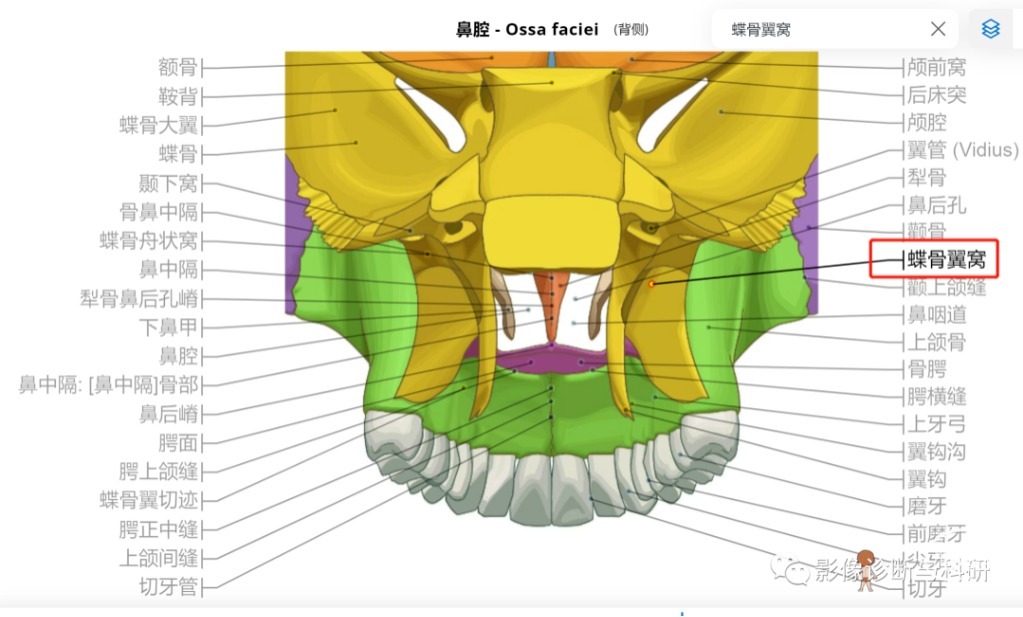

翼窝、颞窝、颞下窝、翼腭窝

1、翼窝(翼突窝)

4、翼腭窝

翼腭窝经8个通道与周围相交通